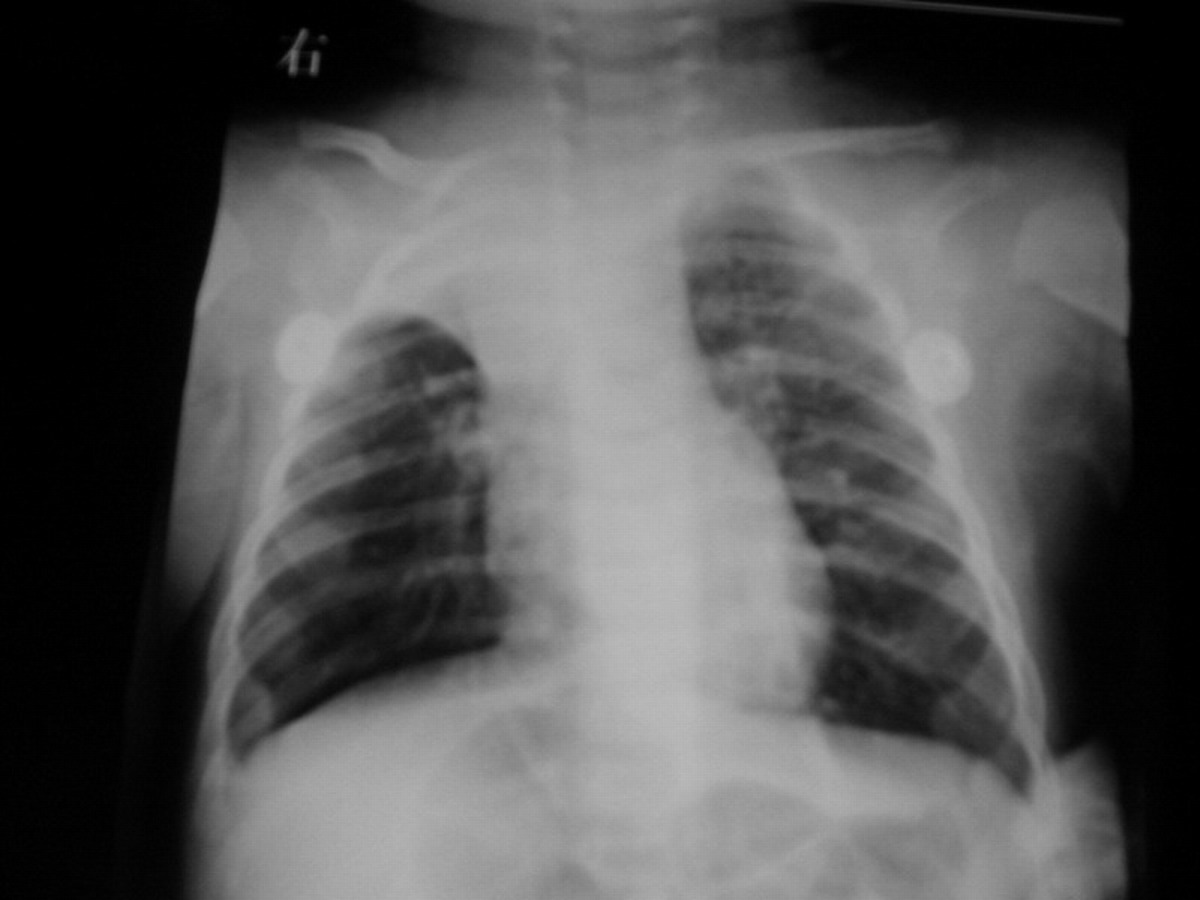

女:4个月,咳嗽4天,喘加重两天。wbc2000 hb73g rbc294

右肺上叶不张。警惕支气管异物!

右上肺不张,右下代偿性肺气肿。尽管支气异物以下叶多见,但此例不能排除异物可能。追问病史或作进一步检查。

右肺上叶不张,左肺见小片状,小点状阴影,支气管肺炎可能性大。建议ct检查以排除肺门淋巴结核

1右肺不张2左上肺散在点状高密度影,左肺门扩大.考虑结核并肺不张可能性大.

右肺上叶肺不张(原因不明);建议:行进一步检查。